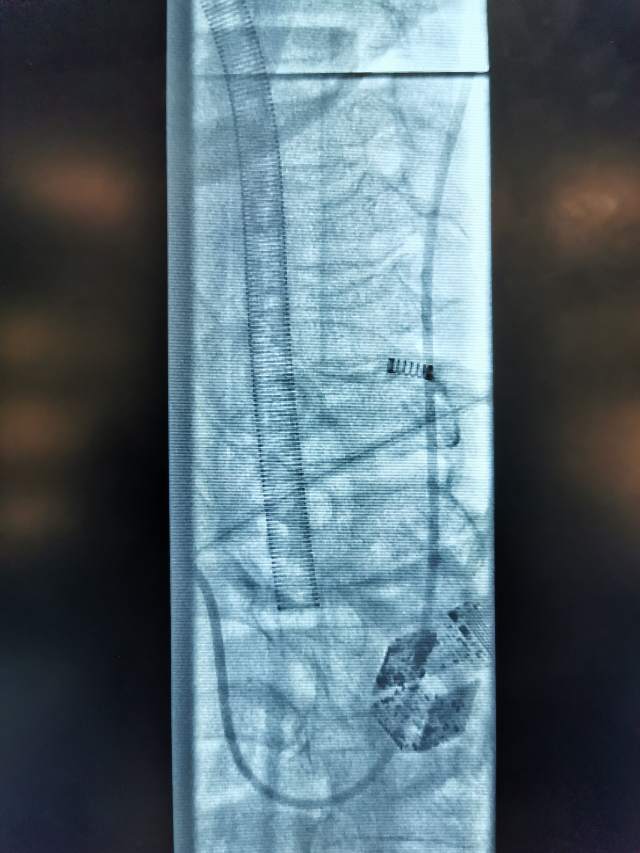

小结:患者颅内后交通动脉瘤导致的动眼神经麻痹,引起眼睑下垂、瞳孔散大、视物重影,眼球外下斜,通过远侧桡动脉入路,克服三型弓的不利解剖因素,顺利治疗了颅内动脉瘤